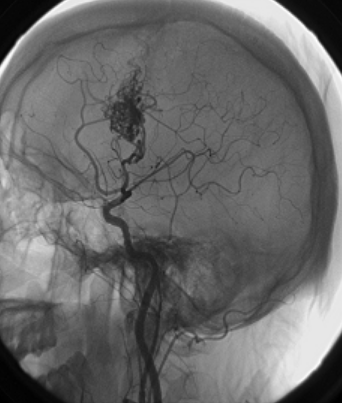

脑动静脉畸形(AVMs)是一种少见的脑血管病变,其特征是大量异常扩张的动静脉和直接动静脉分流。它们通常在青年期发现,并可伴有头痛、癫痫,或较常见的颅内出血,后者可导致的发病率和死亡率。

AVMs可以发生在身体的任何地方,但是大脑和脊髓AVMs在出血时会带来很大的风险。大约50%的患者较初出现出血,死亡率为10-30%;通常有AVM的患者没有症状,他们的AVMs只是偶然发现的,通常是在尸检或治疗无关疾病的过程中发现的。在过去30年中,由于诊断技术的提高,诊断为未破裂的AVMs的患者比例几乎翻了一番。大约12%的AVMs患者的症状在严重程度上各不相同。AVMs会刺激周围的脑组织,引起癫痫或头痛。可能出现下列任何症状:

传统上,脑动静脉畸形的年破裂率为4%,这是根据对症状性动静脉畸形自然史的研究得出的;这项研究还包括先前破裂的脑动静脉畸形。较近一项关于未破裂脑动静脉畸形的随机试验(研究人员较近的其他前瞻性研究报告,未破裂的AVMS每年出血率较低,约为1%,6破裂后出血风险增加,在一年达到6-8%,然后下降到上述初始值。